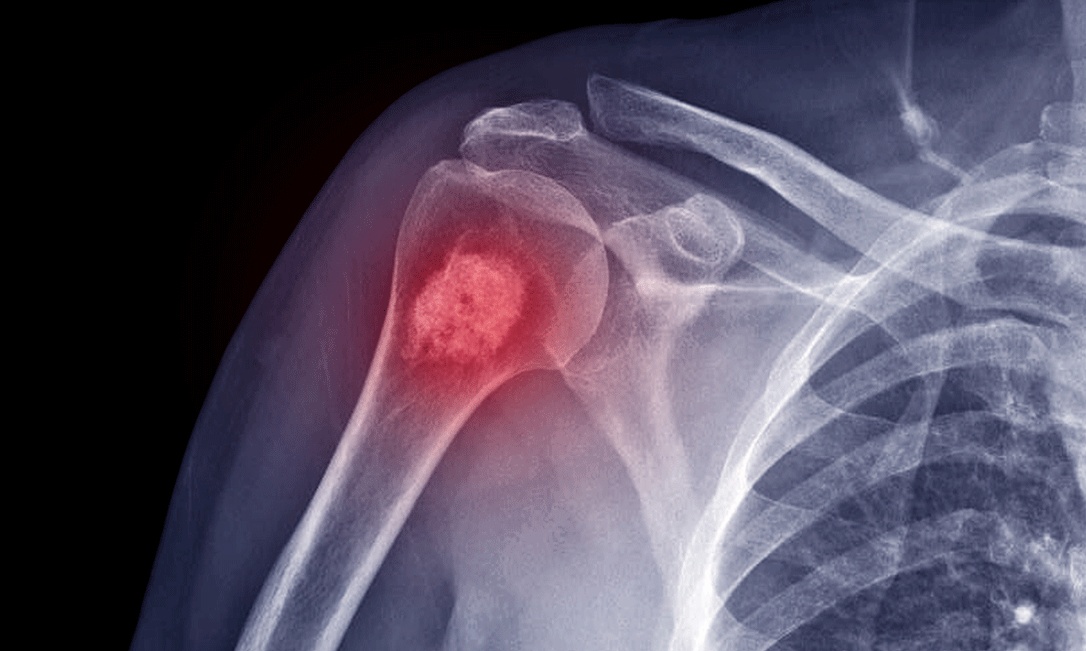

Câncer nos ossos | Foto: Reprodução/Internet

Câncer de ossos, conhecido como sarcoma ósseo, é uma doença agressiva que afeta células e ocorre em qualquer parte do corpo. O principal sintoma é dor óssea crescente e persistente, que pode piorar à noite ou com o uso do osso. Fatores de risco incluem mutações genéticas, exposição à radiação, lesões ósseas e idade (jovens e adultos mais velhos).

Embora seja menos comum do que outras variantes, o câncer de ossos, também conhecido como sarcoma ósseo, é uma patologia de células que começa a crescer sem controle em qualquer parte do corpo. A doença pode ser muito agressiva e exigir tratamentos intensivos, como explica a Sociedade Americana do Câncer.

"O sinal mais comum de câncer de osso é dor no osso afetado. No início, a dor não é constante. Pode piorar à noite ou quando se usa o osso (por exemplo, dor na perna ao caminhar). À medida que o câncer cresce, a dor se torna constante e pode piorar com a atividade”, segundo a sociedade médica.